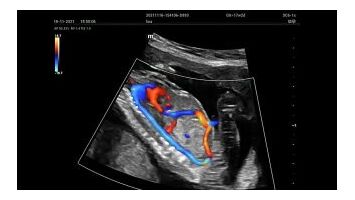

Для эхокардиографии используются секторные фазированные датчики и дополнительные допплеровские режимы с целью исследования сердечной деятельности.

В гинекологии применяются специализированные программы и датчики, позволяющие качественно провести внутриполостные исследования.